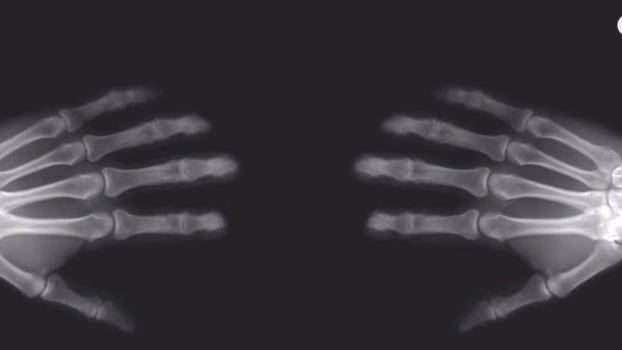

Чудили ли сте се какво се случва, когато изпукате кокалчетата на ръцете си?

От ново видео на Vox научаваме, че характерния звук от това действие всъщност представлява освобождаването на газ.  Какви са ефектите от това?

Повечето научни изследвания по темата откриват малки или абсолютно никакви връзки с артрита. Други обаче твърдят, че това предизвиква подуване, което впоследствие би намалило функционалността ни.